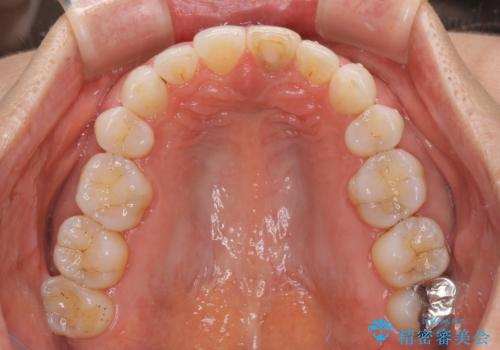

矯正治療の後戻り インビザライン・ライトでの再矯正

- 上下前歯を中心に、以前行った矯正治療の後戻りが気になるとのことで来院された患者様です。

後戻りは軽度であったため、インビザライン・ライトにて治療を行うこととしました。

矯正治療後は、再度後戻りすることを極力回避するために、下顎前歯の舌側を細いワイヤーを用いて保定することとしました。